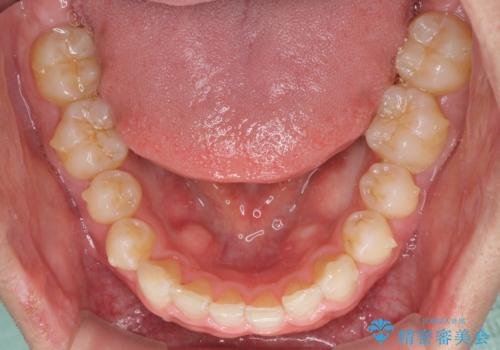

- 上下の前歯の隙間を気にして来院された患者様です。

インビザラインを用い、上下歯列のスペースを閉じていくこととしました。